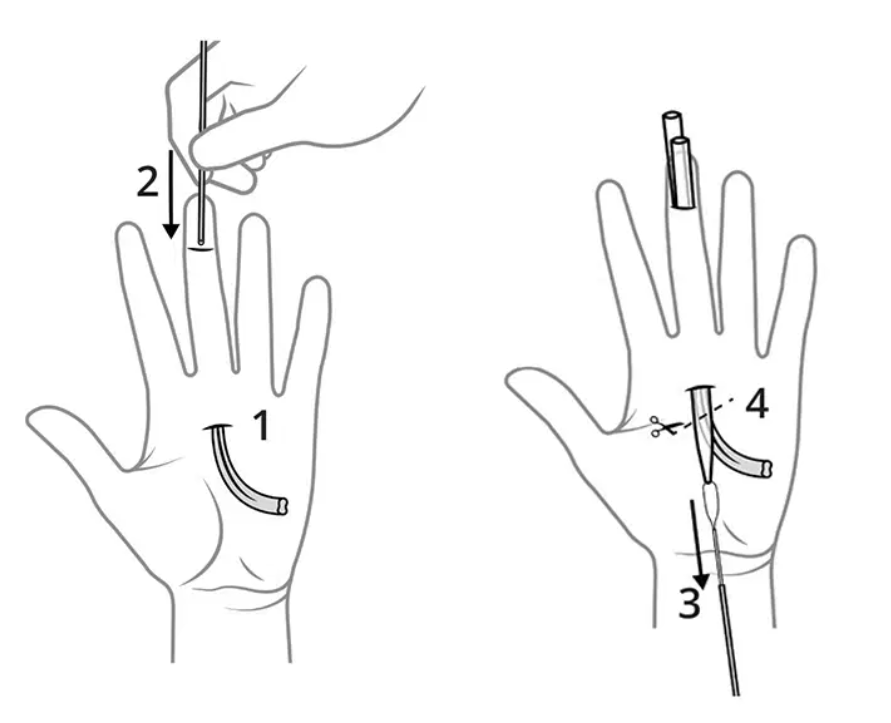

Cây lấy gân gấp ngón tay FlexPasser

Bộ lấy gân gấp ngón tay bao gồm hai phần:

• Đầu dò và giá đỡ kim tích hợp bao gồm một dụng cụ co giãn và kéo dài với một đầu tròn nhẵn, nửa cứng ; đầu kia có tiết diện co giãn để luồn kim cong và chỉ khâu qua ống nhựa.

• Một ống nhựa để lót vỏ bọc của gân bị đứt có vòng chỉ gắn ở đầu ống nhựa, cho phép đầu dò, giá đỡ kim và gân luồn qua vỏ bọc gân từ gần đến xa mà không bị kẹt.